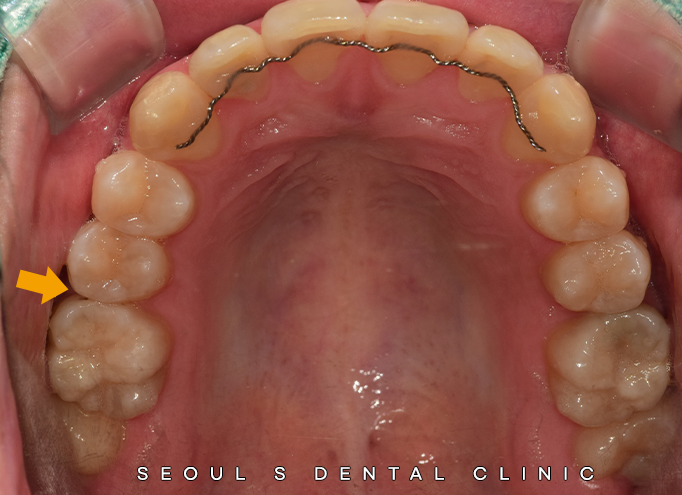

오늘 소개해드릴 분은

20대 남성분으로,

정기검진 중으로 내원하시어

양옆의 첫번째 큰 어금니의

근심쪽 인접면에 (mesial)

충치를 발견할 수 있었답니다.

딱히 불편함 및 증상도 없으셨고,

겉으로 보기에는

별 다른 이상이 없어보였지만,

내부에서는 이미 법랑질이 손상되고 있었습니다.

치아 상태를 환자분께 꼼꼼히 설명드린 후

오른쪽 첫번째 큰 어금니의 근심면은

인레이 치료를 계획하였습니다.

먼저 충치 부위를 깨끗하게 제거하고,

치아의 형태를 정밀하게 다듬은 뒤

인상(본뜨기)을 채득했습니다.

이후 기공소에서

치아 색상과 동일한 인레이를 제작하여,

치아에 정교하게 부착해드렸답니다.

부착 후 경계면이 티가 나지 않고,

가까이서 봐도

어디를 치료했는지 찾기 어려울 정도인데요.

숨은 그림 찾기를 해야할 만큼

자연스럽게 인레이 치료를 도와드린 모습입니다!